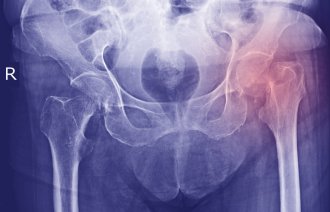

Faktorer som påvirker funksjonsnivået til eldre pasienter operert for hoftebrudd – implikasjoner for målrettede sykepleietiltakFagfellevurdert artikkel